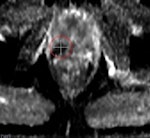

A 48-year-old sexually active male with PSA 9; TRUS biopsy Gleason 4+3 PC at right PZ; stage T1c. Nerve-sparing prostatectomy was performed showing submillimeter ECE and negative resection margins. Postsurgery patient was potent and continent. Left: Axial T2-weighted MR image shows low signal tumor in right PZ (white area) with obliteration of the white fat at the rectoprostatic angle (arrows), indicating minimal ECE = PI-RADS 5. The NVB is indicated by red, blue, and yellow. Right: Nerve-sparing prostatectomy showed Gleason 4+3 PC with submillimeter ECE (T; blue area) at right PZ. Resection margins were negative. Patient was potent after surgery.

A 48-year-old sexually active male with PSA 9; TRUS biopsy Gleason 4+3 PC at right PZ; stage T1c. Nerve-sparing prostatectomy was performed showing submillimeter ECE and negative resection margins. Postsurgery patient was potent and continent. Left: Axial T2-weighted MR image shows low signal tumor in right PZ (white area) with obliteration of the white fat at the rectoprostatic angle (arrows), indicating minimal ECE = PI-RADS 5. The NVB is indicated by red, blue, and yellow. Right: Nerve-sparing prostatectomy showed Gleason 4+3 PC with submillimeter ECE (T; blue area) at right PZ. Resection margins were negative. Patient was potent after surgery.One in six men in their lifetime will be clinically diagnosed with prostate cancer, and this accounts for 350,000 cases, annually or 25% of all new male malignancies diagnosed in Europe, the authors noted. Currently, digital rectal examination, serum prostate specific antigen (PSA) -- a nonspecific blood test -- and transrectal ultrasound-guided biopsy -- where the target is mostly invisible -- are used as diagnostic tools.